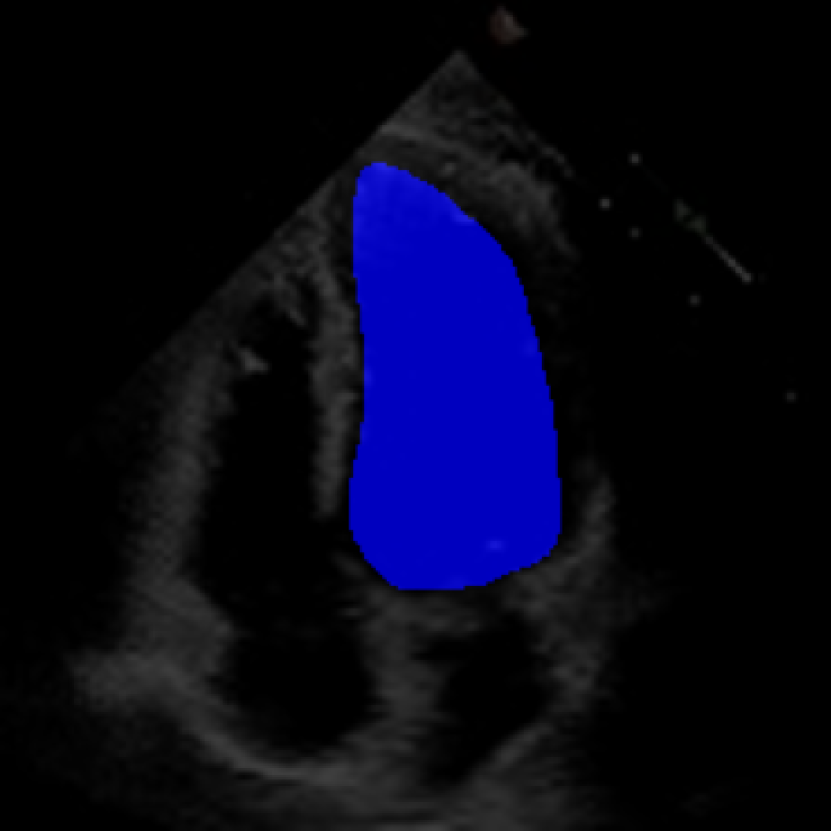

The 112x112 input is first resized to 299x299 as required by the Xception model. The Beat Extractor is then used to feed only whole beats to the LVEF estimation pipeline. A modified DeepLabV3+ model segments the left ventricle for every frame of the echocardiogram video (Figure LABEL:fig:segmentation). The area is measured, and a peak detector is then used to find the maximum (diastole) and minimum area (systole). The frame numbers corresponding to these extrema are recorded, and the video is clipped into smaller videos that go from diastole to systole. These smaller videos are independently fed to the Xception based feature extractor.

The ConFormer model demonstrated high performance in the estimation of Left Ventricular Ejection Fraction (LVEF) from echocardiogram videos (Figure 2). The model achieved a mean absolute error of 6.57 in LVEF prediction, indicating a high level of accuracy in its estimations (Table I). Notably, ConFormer outperforms the full video assessment of LVEF by EchoNet-Dynamic, a significant achievement given the model’s efficiency. With just 5.82 million parameters, ConFormer is significantly more efficient than existing models, making it a practical tool for real-world applications.